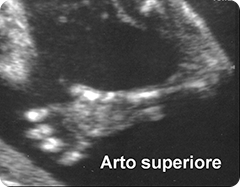

arti: valutazione delle ossa lunghe e delle mani e dei piedi (presenza/assenza); misura della lunghezza del femore